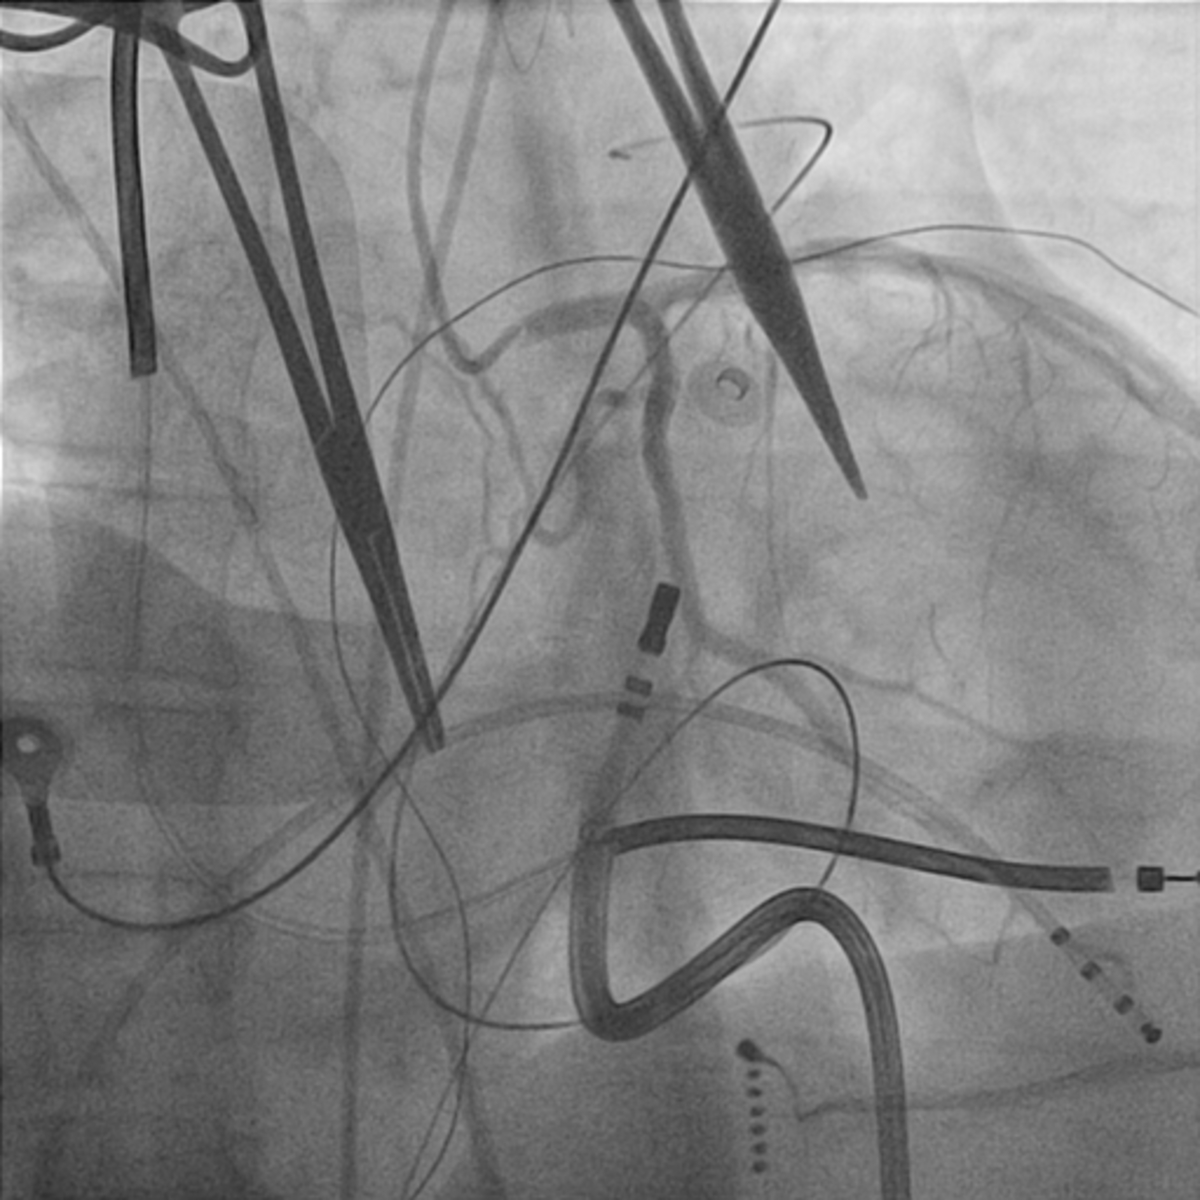

Setup

IMG7.jpg